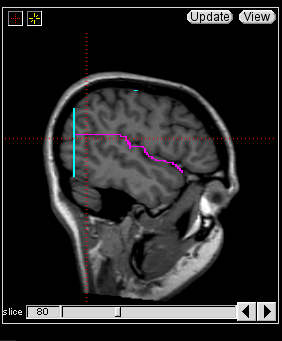

The insular cortex is “hidden” between the temporal and inferior parietal corticies. By drawing sulci lines in the sagittal view, we gain an outline of it in the coronal. Choose a sagittal slice where insula is clearly visible (Fig 1), then draw a “circle” around it (Fig 2). Do this for several slices and for both hemispheres.

Figure 1              Figure

2